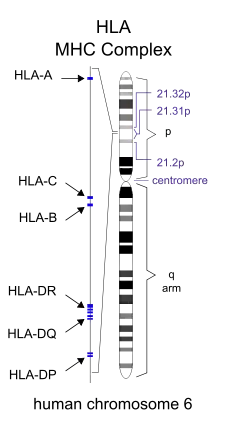

Specific genes that have been linked with MS include differences in the human leukocyte antigen (HLA) system—a group of genes on chromosome 6 that serves as the major histocompatibility complex (MHC).[1] That differences in the HLA region are related to susceptibility has been known since the 1980s,[60] and this same region has also been implicated in the development of other autoimmune diseases, such as diabetes type I and systemic lupus erythematosus.[60] The most consistent finding is the association between higher risk of developing multiple sclerosis and the MHC allele DR15, which is present in 30% of the U.S. population and Northern European population.[15][1] Other loci have shown a protective effect, such as HLA-C554 and HLA-DRB1*11.[1] HLA differences account for an estimated 20 to 60% of the genetic predisposition.[60] Modern genetic methods (genome-wide association studies) have revealed at least 200 variants outside the HLA locus that modestly increase the probability of MS.[61]